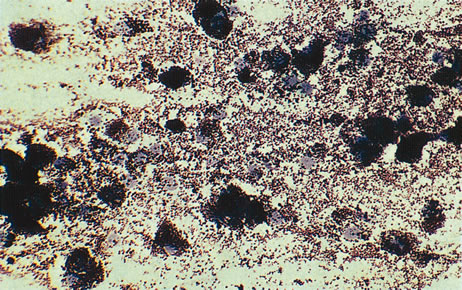

Figure 16 shows a case of what clinically and ultrasonographically appeared to be a uveal melanoma. The FNAB specimen revealed a cellular pattern that was diagnostic of a primary carcinoid (Fig. 17), and the patient responded dramatically with 40 gray of photon radiation. Figure 18 shows the FNAB cytopathology of a typical epithelioid choroidal melanoma; in contrast, a smear of a spindle cell tumor has spindle-shaped cytoplasm and smaller nuclei. Figure 19 shows a benign pigmented mass, such as a retinal pigment epithelial proliferation or a melanocytoma. In contrast to a melanoma, this type of mass has much larger pigment granules and benign cytomorphologic detail. In addition to standard cytopathologic FNAB evaluation, aspirated material may be used for several molecular biology studies (e.g., fluorescence in situ hybridization, comparative genomic hybridization), flow cytometry, special stains, tissue culture, and ultrastructural analyses.